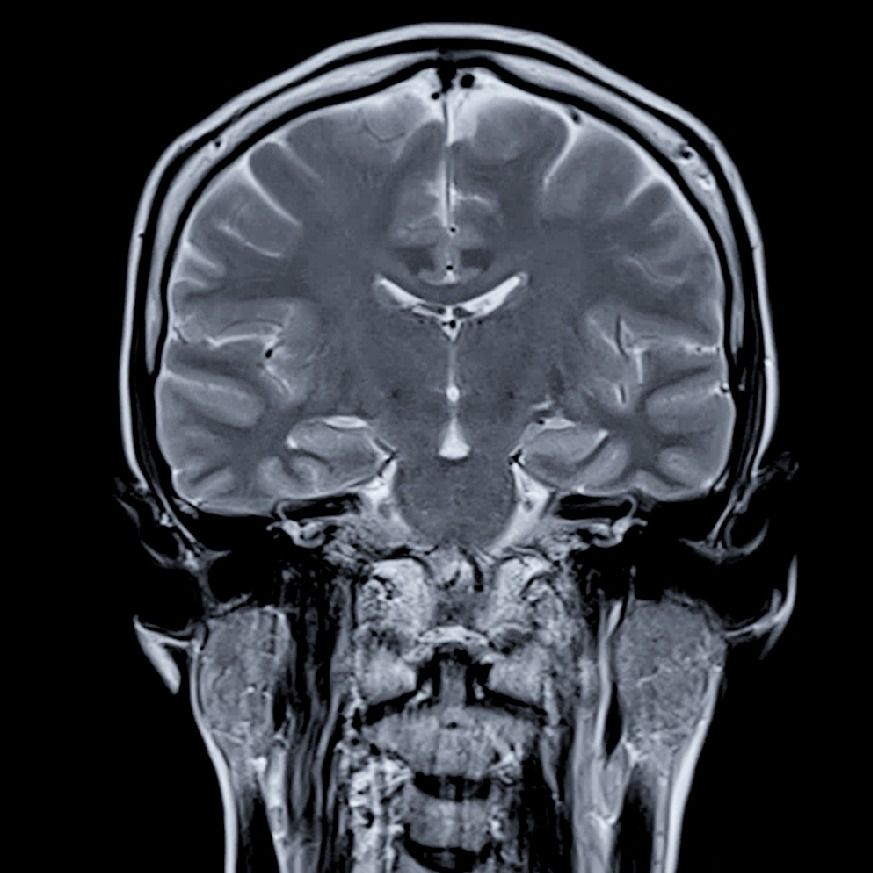

One of the key differences between the two systems lies in image clarity and noise levels. A 3T magnet provides nearly double the SNR of a 1.5T system, allowing for either higher resolution or faster scan times. This makes it especially advantageous for detailed brain imaging, musculoskeletal exams, and small lesion detection. However, higher field strength also increases artifacts such as susceptibility, dielectric shading, and inhomogeneity—especially in areas like the abdomen, pelvis, and spine. In contrast, 1.5T systems tend to produce cleaner images in these regions, with more reliable fat suppression and fewer distortion issues near metal implants.

In stroke imaging, particularly diffusion-weighted imaging (DWI), both field strengths can produce diagnostically effective results. However, 3T offers slightly higher sensitivity to early ischemic changes. That said, 1.5T scanners often provide more stable ADC (apparent diffusion coefficient) maps with less distortion, which can be clinically beneficial, especially when post-processing is applied to enhance contrast and suppress background noise. Advanced post-processing software—such as AI-based denoising algorithms, motion correction, and parallel imaging techniques like GRAPPA or SENSE—can elevate 1.5T DWI quality to nearly 3T standards in many cases.